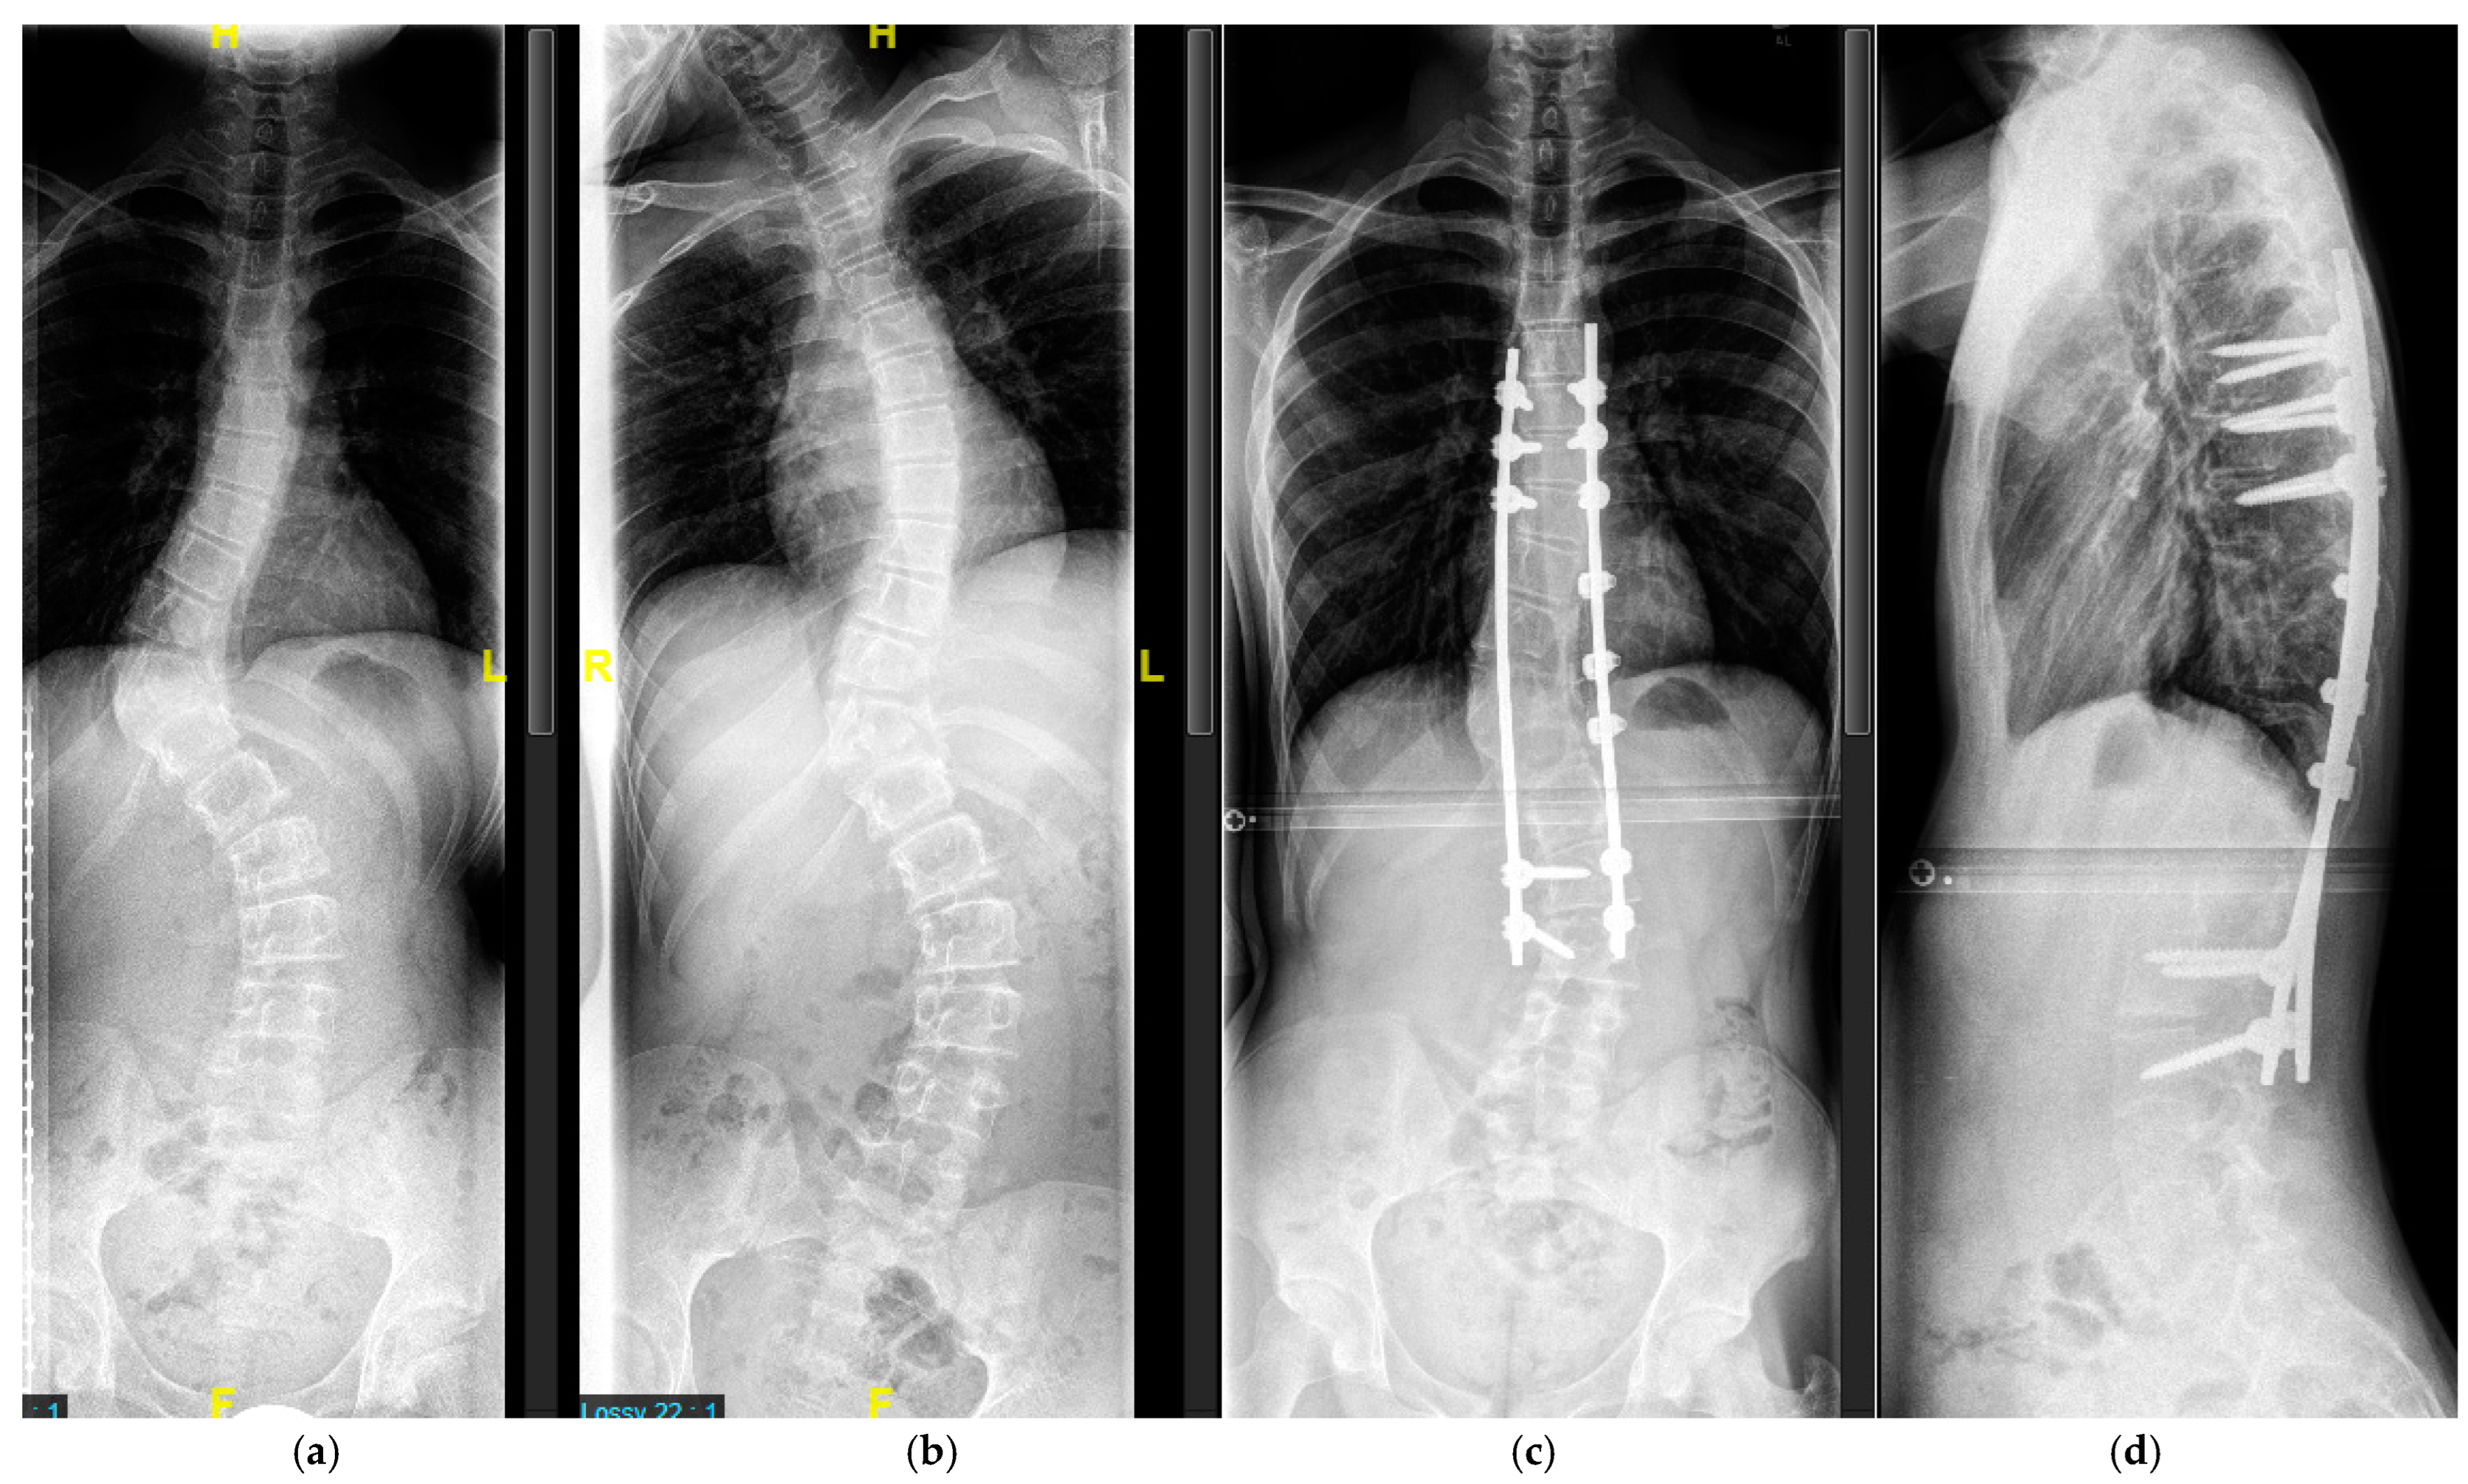

4.2.1. “Early Onset Spinal Deformity”

4.2.2. Adolescent Spinal Deformity

5.2.1. Growth-Preserving Techniques

5.2.2. Definitive Spinal Fusion